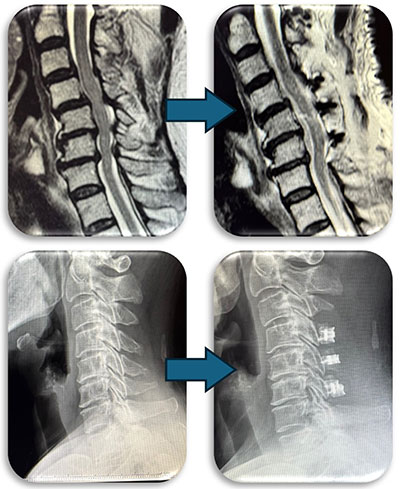

(代表例②)

頚部にできた血管奇形の症例です。当初脊髄腫瘍という話で紹介された症例でしたが、巨大な血管奇形でした(赤矢印)。椎骨動脈と脊柱管内の静脈に異常なシャントが原因で巨大な静脈瘤を呈し、それが脊髄を圧迫し神経症状を来していました。この症例はもともと神経繊維腫症1型という遺伝子疾患の既往があったのですが、まれに頚椎や頚椎周囲の血管に奇形を呈することがあります。このような症例は外科的治療は危険性が非常に高く、血管内治療で治療しました。なお、この症例は環軸椎亜脱臼も呈しており今後時期を診て脊椎手術も行う予定です。